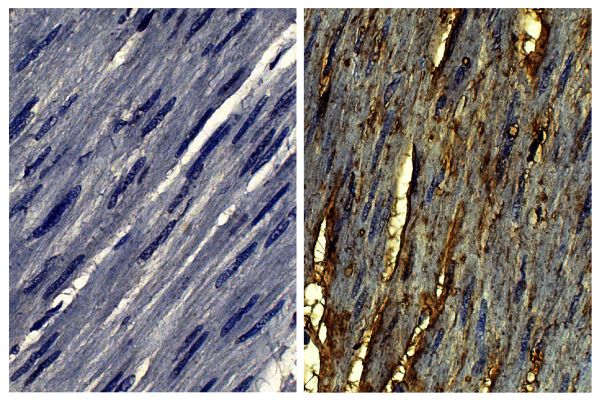

Swine Anti-Goat IgG(H+L)-Biotin antibody with minimal reactivity to human, mouse, and rat serum proteins for use in ELISA, flow cytometry, immunohistochemistry, and western blot assays.

Quality tested applications for relevant formats include - ELISA FLISA Other referenced applications for relevant formats include - Flow Cytometry 1,2 Immunohistochemistry-Frozen Sections 3 Western Blot 4-7 |

- 3. Zone JJ, Schmidt LA, Taylor TB, Hull CM, Sotiriou MC, Jaskowski TD, et al. Dermatitis herpetiformis sera or goat anti-transglutaminase-3 transferred to human skin-grafted mice mimics dermatitis herpetiformis immunopathology. J Immunol. 2011;186:4474-80. (IHC-FS)